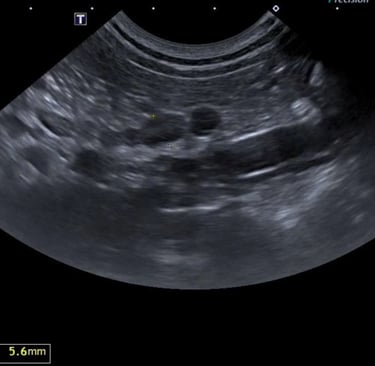

10 - De quel organe s'agit-il ?

A - Le Foie

B - La Rate

C - La Prostate

D - Le Jéjunum

E - Le Pancréas

11 - Sur cette même image échographique que pouvez-vous dire ?

A - J'observe la présence d'une hyperéchogénicité du parenchyme

B - Je n'observe aucune anomalie

C - J'observe la présence d'une hypoéchogénicité du parenchyme

D - J'observe la présence d'un effet de masse

12 - De quel organe s'agit-il ?

Question 10 : Réponse B

Question 11 : Réponse B